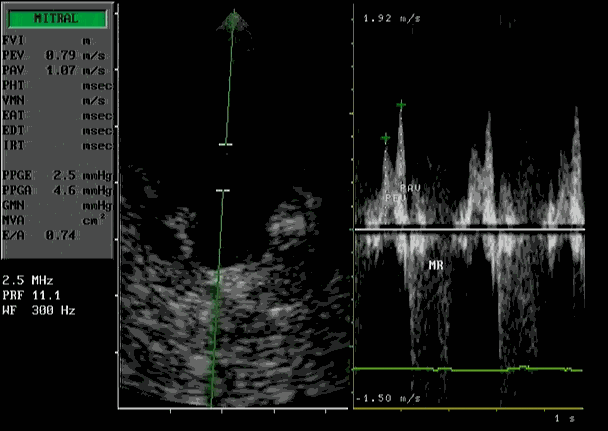

Doppler bij HCM:

Hierbij wordt het flow patroon door de mitraalklep zichtbaar gemaakt bij verminderde contractie van de hartspier. De pieksnelheid tijdens de vullingsfase is verminderd, de snelheid na de contractie van de linker boezem is toegenomen.

Dynamische outflow obstructie

Kleuren Doppler

Laat zien, dat het uitstroom-gebied van de linker kamer is vernauwd